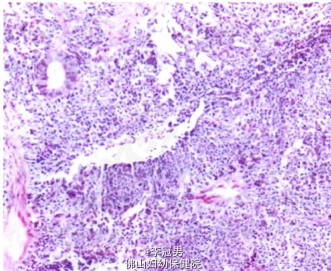

术前诊断:右侧卵巢肿瘤。 处理:在全身麻醉下行开腹探查手术。术中见盆腔无腹水,子宫、双侧卵巢及左侧输卵管均正常,右侧输卵管自壶腹部增粗形成一大小为9.0 cm×8.5 cm×5.0 cm囊肿,表面光滑,包膜完整。术中未行快速冰冻病理检查,行右侧输卵管囊肿剔除术。术后给予对症支持治疗。术后病理检查示:右侧输卵管交界性乳头状囊腺瘤,部分区域癌变,局灶呈肉瘤样分化。2日后,在全身麻醉下行腹腔镜下右侧附件切除术+盆腔淋巴结切除术+大网膜切除术+阑尾切除术+左侧卵巢活检术。术后病理检查示:输卵管交界性乳头状肿瘤(见图1),由浆液性及子宫内膜样上皮成分构成,局部癌变(直径0.2 cm)(见图2),部分分化较差,呈肉瘤样癌结构(见图3)。免疫组化:AEI/AE3(分化较好区+++,分化差区+),CK7(分化好区+,分化差区一),CK20(分化较好区+,分化较差区一),R(一),Vimentin(+),Ki-67指数15%一30%。卵巢、阑尾、大网膜及盆腔淋巴结均未见肿瘤(0/30)。术后诊断为:右侧输卵管恶性苗勒管混合瘤。术后给予卡铂+紫杉醇3疗程化疗。

患者术后6个月定期随访无特殊不适。 讨论:恶性苗勒管混合瘤(MMMT)是女性生殖道恶性肿瘤之一,是罕见的高度恶性肿瘤。该肿瘤最常见于子宫内膜,其次是阴道、官颈、卵巢,输卵管最少见,仅占所有MMMT的4%。多数患者为50—60岁的绝经后女性,平均年龄57.5岁。其典型组织学特点为癌和肉瘤样成分混合存在,癌样成分常为子宫内膜样、透明细胞样或乳头状浆液性,分化较差;肉瘤样成分似平滑肌肉瘤或纤维肉瘤,半数以上可出现骨骼肌、骨、软骨或脂肪等异源性成分输卵管癌变往往没有典型的临床症状,以往以盆腔包块、阵发性阴道排液和腹痛“三联征”作为输卵管癌的术前诊断依据。但近年来发现临床上同时出现“三联征”的病例并不多,而以盆腔包块伴阴道排液或阴道不规则流血的“二联征”多 见。本例患者术前也没有明确的“三联征”表现,而是以停经及盆腔包块为主要的临床表现,实属少见,最终患者因“附件肿瘤”进行手术,术中发现病变源于输卵管,术后病理检查提示输卵管交界性乳头状肿瘤,由浆液性及子宫内膜样上皮成分构成,局部癌变,部分分化较差,呈肉瘸样癌结构,符合MMMT的病理学诊断。